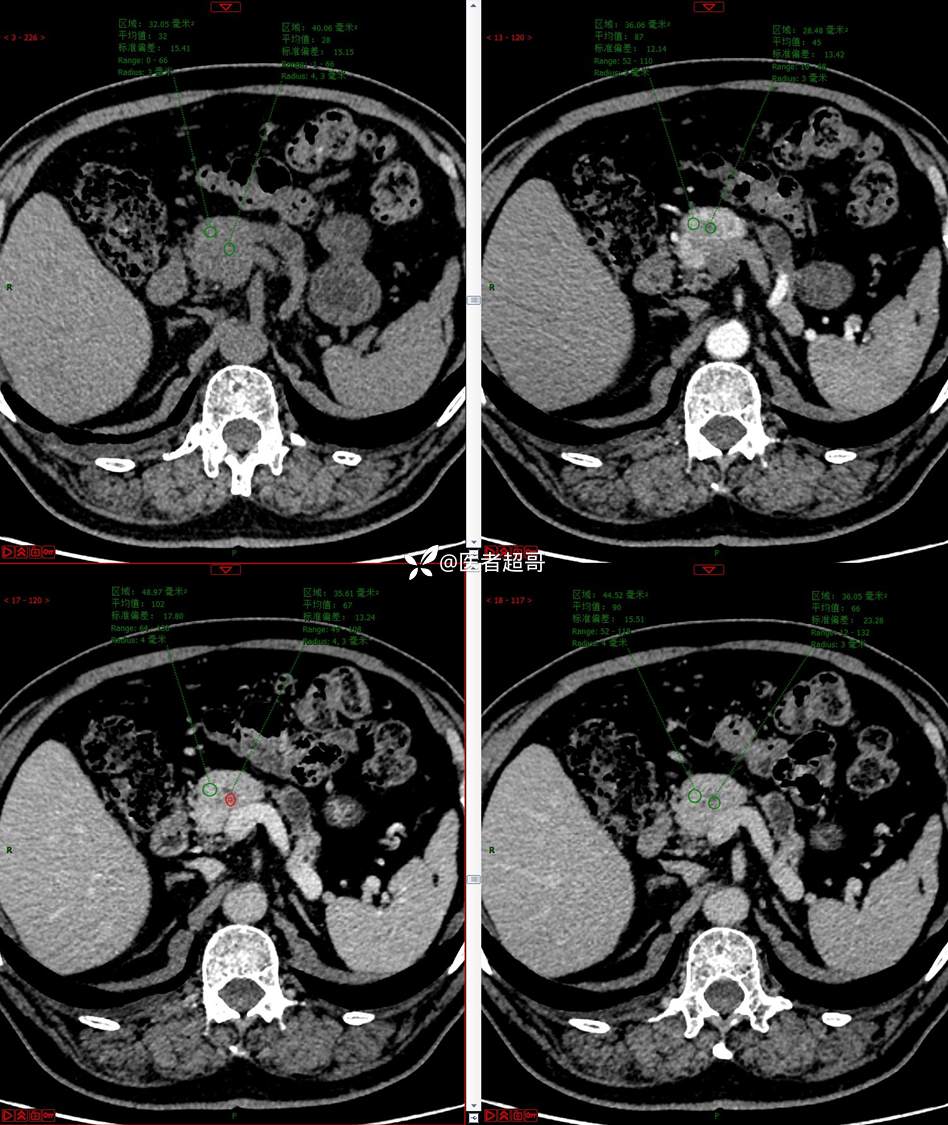

【影诊笔记677】查体发现胰腺占位性病变1周,细节决定成败,请诊断分析!

主 诉:查体发现胰腺占位性病变1周。

现病史:患者1周前在当地查体时发现胰腺占位性病变,无恶心、呕吐,无腹痛,无寒战、高热,无咳嗽、咳痰等异常不适,来我院门诊查上腹部CT平扫+强化:胰腺尾部异常密度灶。今为求进一步治疗,门诊以“胰腺占位性病变”收入院。患者自发病以来,一般情况可,神志清,精神可,普通饮食,二便正常,体重及体力无明显改变。

既往史:既往糖尿病病史2年,口服二甲双胍早晚各一片和格列吡嗪早晚各一片,否认高血压、心脑血管病等疾病史,否认肝炎、结核或其他传染病史及密切接触史,预防接种史不详,否认药物及食物过敏史,否认外伤史,12年前肾癌切除术手术史,否认输血史,其它无特殊。